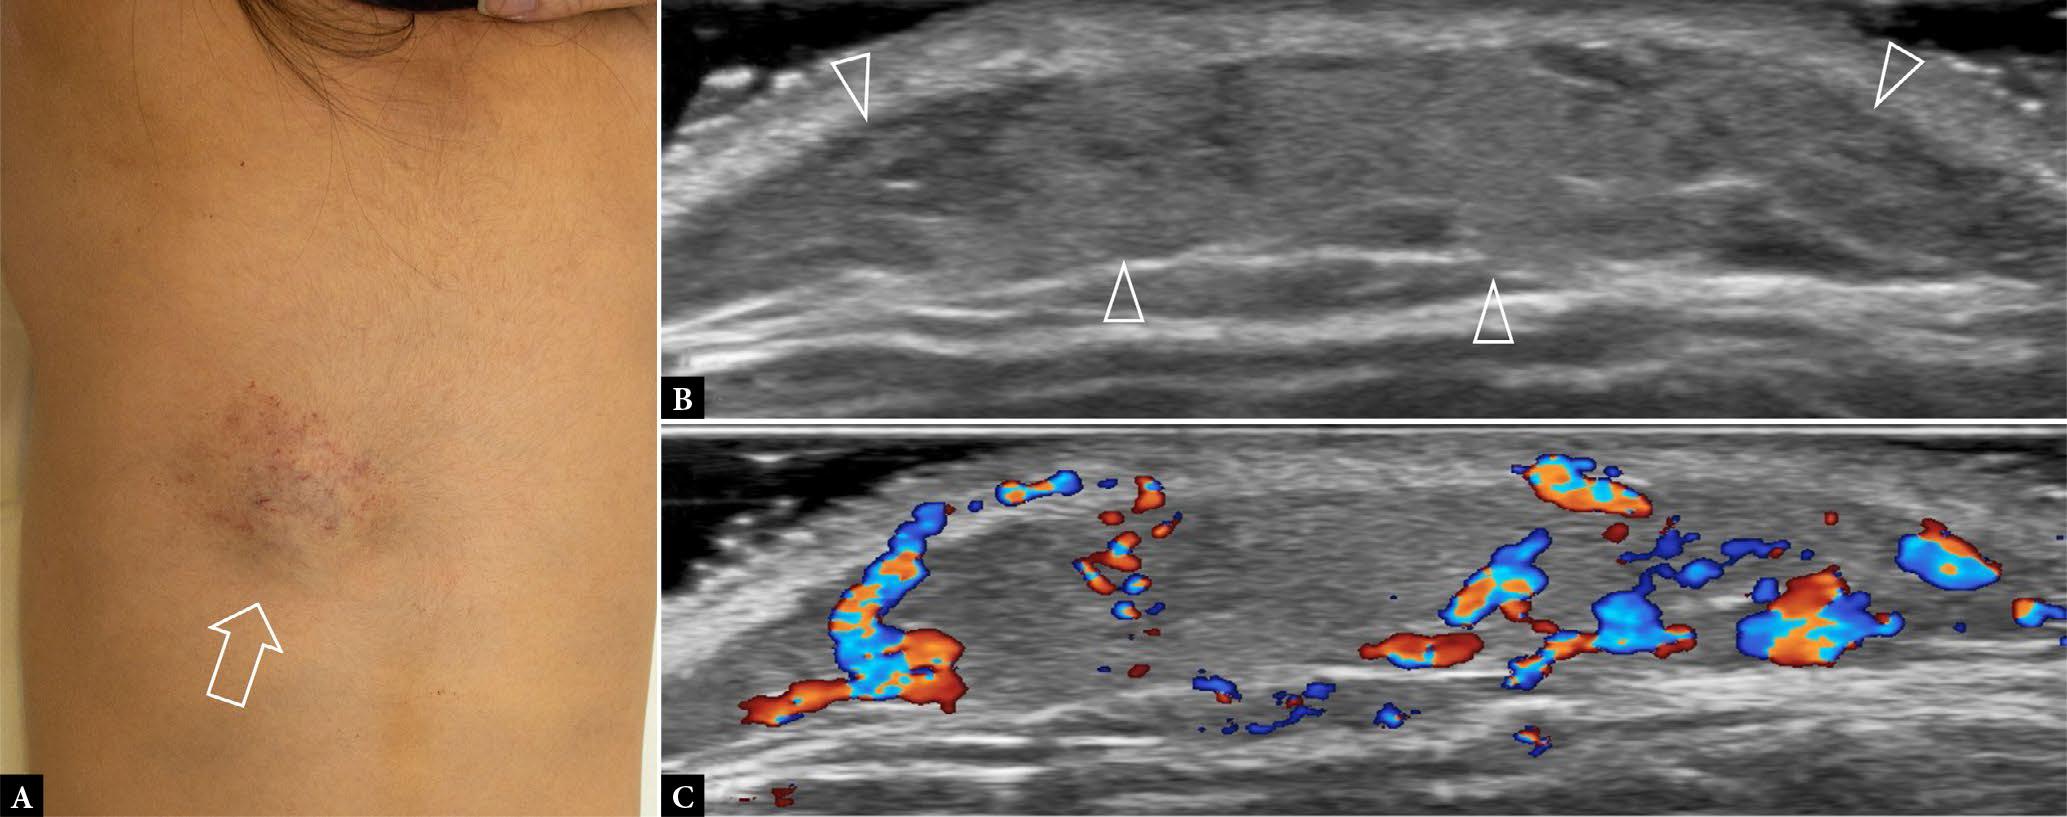

Fig. 3.

4-year-old female with mass, deep to colored birthmark on dorsal aspect of trunk, enlarging over the past two years A. Clinical photograph shows the site of mass (arrow). Transverse B. greyscale and C. color Doppler US shows a medium-sized moderately hyperemic vascular anomaly involving the skin and subcutaneous tissues (arrowheads), most likely either venocapillary vascular malformation or hemangioma. No deep extension present. Follow-up US will be performed in two years to assess for further commensurate growth (favoring vascular malformation) or involution (favoring hemangioma)